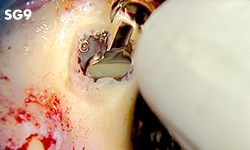

SINUS LIFT

Contenido

• SG1, SG3, SG6D, SG9, SG10, SG11

• Soporte para puntas